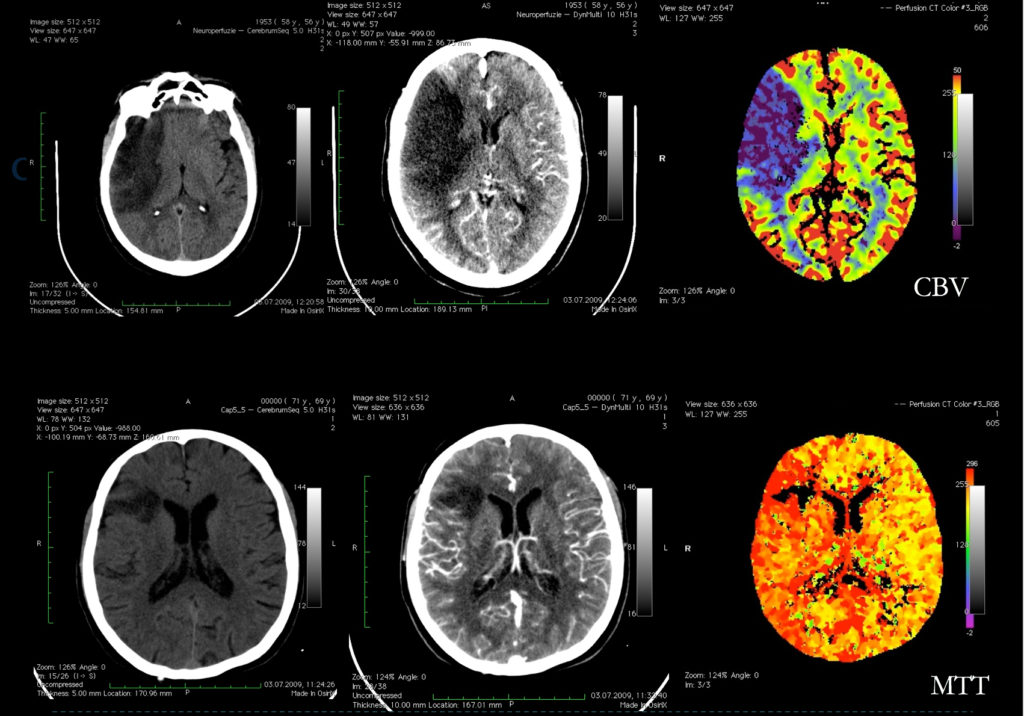

Perfuzie CT

Perfuzia IRM şi CT (PWI) aduc indicii asupra parenchimului cerebral și asupra funcţiei cerebrale prin măsurarea unor parametri hemodinamici precum: volumul sangvin cerebral, fluxul sangvin cerebral şi timpul mediu de tranzit.

În imagistica de perfuzie se obţin o serie de imagini ale teritoriilor arterelor cerebrale medii după administrarea i.v. a substanţei de contrast, iar modificările de atenuare (priza de contrast) a parenchimului cerebral se măsoară în timp.

Perfuzia CT permite diferenţierea ariilor de infarctizare reală (nucleul ischemic) de ariile ischemice care sunt supuse riscului de infarctizare în lipsa terapiei trombolitice (zona de penumbră).

- în identificarea nucleului infarctului – regiuni cu CBV (volum sanguin cerebral) extrem de scăzut;

- în identificarea pacienților care prezintă zone de “țesut cu risc de infarctizare” în absența recanalizării, care pot fi recuperate cu tratament trombolitic (la debutul unui AVC acut, prezenţa unei zone de penumbră ischemică operațională reprezintă o indicaţie că terapia trombolitică poate fi benefică);